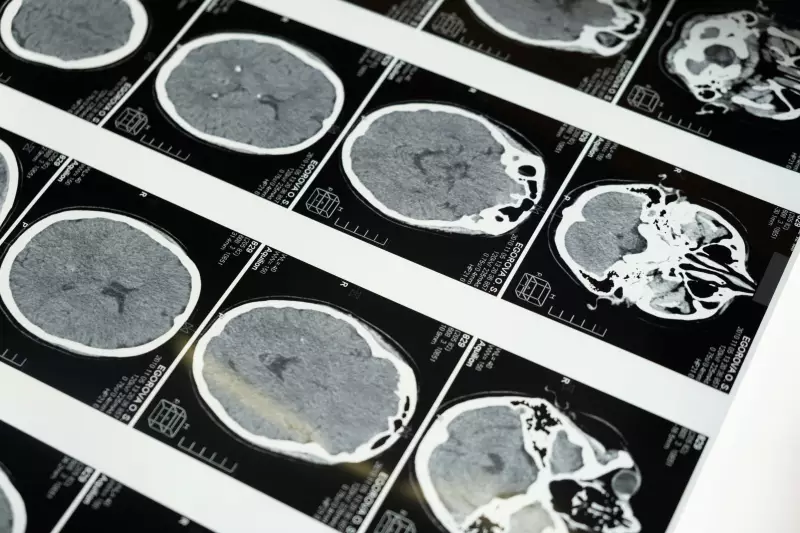

As doenças priônicas ocorrem quando proteínas normais do cérebro, chamadas príons, sofrem uma mudança estrutural fatal. Essas proteínas "dobradas errado" tornam-se infecciosas e desencadeiam uma reação em cadeia que destrói neurônios.

Embora extremamente raras, com cerca de 1 a 2 casos por milhão de pessoas anualmente, essas doenças continuam sendo um dos maiores mistérios da neurologia moderna, desafiando pesquisadores a desvendar os segredos dessas proteínas assassinas.